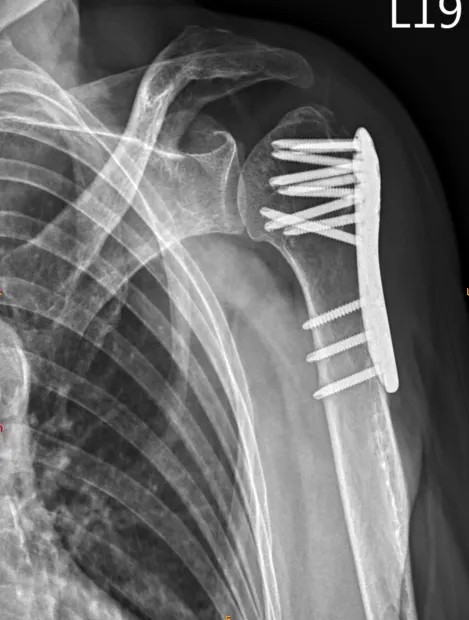

肱骨骨折 之併發症 後遺症 建議與治療 – 松山景能物理治療所

2025/10/22肱骨骨折 是指上臂骨肱骨斷裂的情況,根據骨折的位置和方式,可以分為以下幾種類型:

鑑於肱骨骨折的不同類型,治療方法和康復過程也可能有所不同,因此必須對患者進行詳細的評估和診斷。